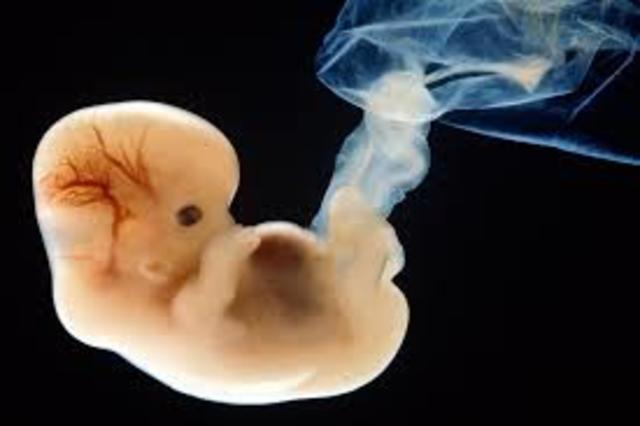

3-8 weeks the umbilical cord extends from the embryo and connects to the placenta.The egg is fertilized. The amniotic fluid is beginning to collect around the ball of cells in the cavity that will become the amino sac.